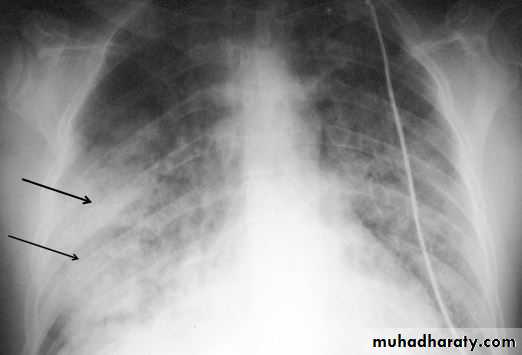

A/F level with mediastinal shift

Chest tube